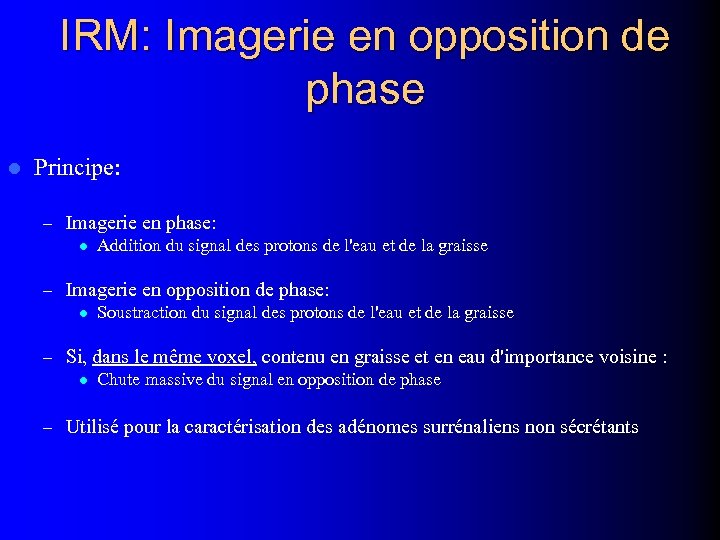

IRM: Imagerie en opposition de phase l Principe: – Imagerie en phase: l Addition du signal des protons de l'eau et de la graisse – Imagerie en opposition de phase: l Soustraction du signal des protons de l'eau et de la graisse – Si, dans le même voxel, contenu en graisse et en eau d'importance voisine : l Chute massive du signal en opposition de phase – Utilisé pour la caractérisation des adénomes surrénaliens non sécrétants

IRM: Imagerie en opposition de phase l Principe: – Imagerie en phase: l Addition du signal des protons de l'eau et de la graisse – Imagerie en opposition de phase: l Soustraction du signal des protons de l'eau et de la graisse – Si, dans le même voxel, contenu en graisse et en eau d'importance voisine : l Chute massive du signal en opposition de phase – Utilisé pour la caractérisation des adénomes surrénaliens non sécrétants